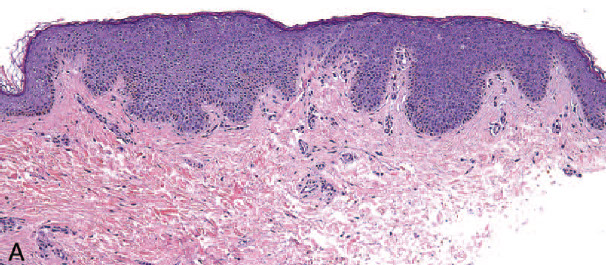

Differentiated VIN

A, Differentiated vulvar intraepithelial neoplasia (dVIN) with marked nuclear atypia and hyperchromasia of the basal cell layer. P53 immunostaining is strongly positive in the lower one-third to two-thirds of the epithelium (B) (hematoxylin-eosin, original magnification x20 [A]; original magnification x20 [B]).

Micro: epidermis of dVIN usually thick and hyperkeratotic and/or parakeratotic with elongated and anastamosing rete ridges

- the basal cells show atypical, hyperchromatic nuclei often with inc mits

- upper layers made of enlarged squamous cells with abundant eosinophilic cytoplasm

Differentiated or Simplex subtype of VIN (dVIN) is a unique subtype seen in post-menopausal women presenting as an ill-defined gray-white plaque associated with lichen sclerosus, and more likely than warty to progress to invasive SCC and is high-grade by definition (regardless of extent of maturation)

- may not be recognized if bx too superficial, not assoc c HPV, assoc c cigarette smoking;

- usually a difficult dx to make bc often has overlapping features with b9 hyperplasia, lichen sclerosus and lichen planus

- frequently have p53 mutations